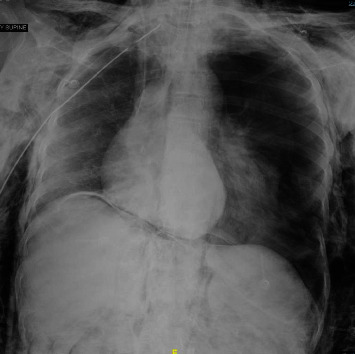

呼吸暂停测试是诊断脑死亡或更具体地说是脑干死亡的标准方法;然而,必须认识到在此过程中可能会造成肺损伤,并遵循可降低并发症风险的临床实践指南建议。有两例气压创伤导致气胸的病例是在使用高于建议氧流量的呼吸暂停测试中发生的。需要更多的数据来明确这种危及生命的并发症的机制和发生率。

Apnea testing is a standard method when diagnosing brain or more specifically brainstem death; however, it is imperative to acknowledge the potential for lung injury during this procedure and follow clinical practice guideline recommendations that may reduce the risk of complications. Two cases of barotrauma leading to pneumothorax occurred during apnea tests that used higher-than-recommended oxygen flow rates. Additional data are necessary to clarify the mechanism and incidence of this life-threatening complication.